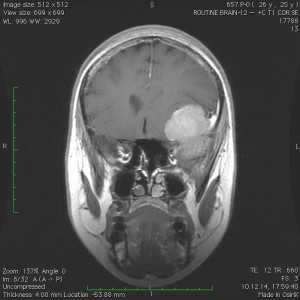

Пациентка В., 25 лет. В возрасте 9 лет перенесла острый лимфобластный лейкоз, по поводу чего проводилась лучевая терапия.

За 2 месяца до поступления в стационар появилась боль в левой височной области, левом глазном яблоке, слезотечение. Консультирована офтальмологом — выявлено высотные левого глазного яблока на 6 мм, по сравнению с правом глазным яблоком, а также признаки внутричерепной гипертензии в виде застойных дисков зрительных нервов. При МРТ выявлена больших размером внемозговая опухоль средней черепной ямки с гиперостозом и распространением в глазницу слева.

Выполнена операция — удаление менингиомы крыльев клиновидной кости с резекцией гиперостоза и использоваием интраоперационной метаболической навигации (ультрафиолетовая флюоресцентная микроскопия)